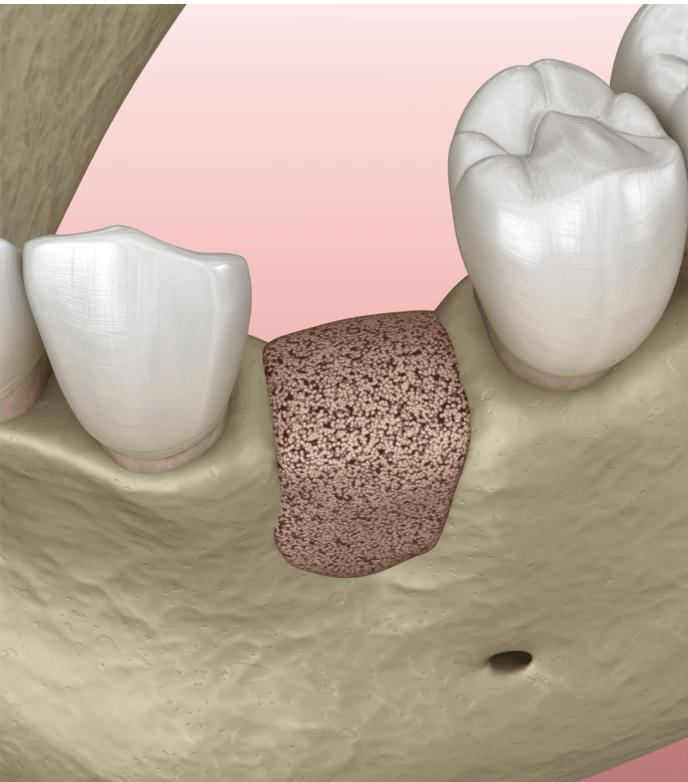

Voir plusComprendre la greffe osseuse dentaire et son importance

Une greffe osseuse dentaire peut sembler complexe à première vue, mais son importance dans le domaine de l’odontologie est indéniable. Plongeons...

Voir plusGreffe osseuse réussie : guide complet

La décision de subir une greffe osseuse dentaire peut être le premier pas vers un sourire restauré et une santé bucco-dentaire...